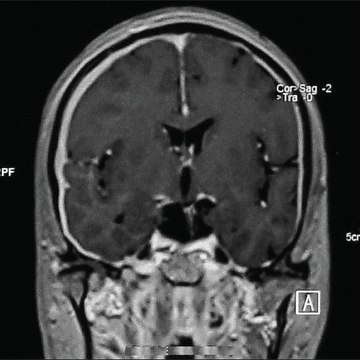

Pachymeningitis

Pachymeningitis - http://goo.gl/4w4Gf9